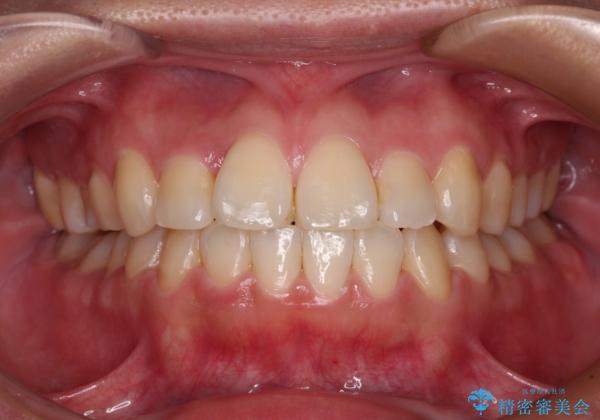

- 前歯のデコボコとクロスバイトを気にして来院された患者様です。

骨格的に下顎が前方位の受け口傾向であり、それが原因でクロスバイトとなっていました。

なお、右奥の歯が180度回転した状態で萌出しており、こちらは改善困難なため、そのままの向きで配列することとしました。